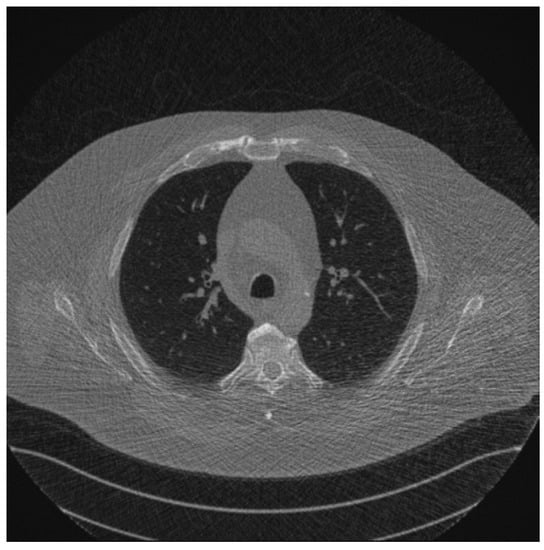

2.2. Data and Modeling